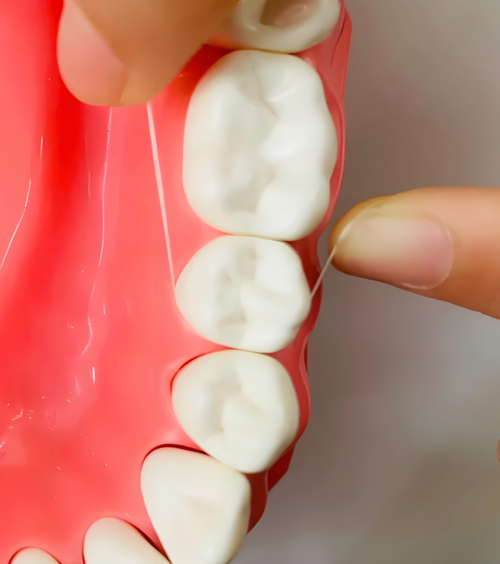

图片42.png

图2:展示牙线以“C”字形环绕牙齿侧面,清洁牙龈沟和邻面区域的示意图。